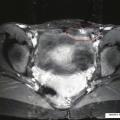

La tomodensitométrie n’est pas un bon examen pour diagnostiquer le nodule endométriosique pariétal dans la cicatrice de césarienne (fig 2).27 L’imagerie par résonance magnétique est plus adaptée pour l’exploration de la région pelvienne ; elle permet de rechercher une endométriose pelvienne dans le même temps qu’elle détermine les dimensions et la localisation précise du nodule endométriosique dans la paroi (fig. 3).30, 31